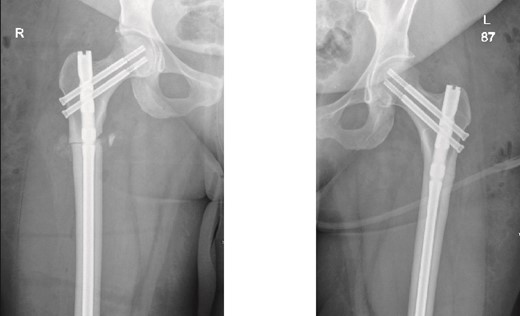

The patient was seen in the clinic at 2 weeks, 6 weeks, and 6 months post-surgery. She was doing well, reporting only mild pain. She was fully weight-bearing with the assistance of a cane and had good range of motion (Figs 3 and 4).

6-months follow-up anteroposterior (AP) view of the right and left femurs after CRIF with IM nail.

As part of the follow-up, the endocrinology team continued to monitor the patient for further investigation into the possible causes of the fractures. A BMD scan was performed and showed normal results. Based on their assessment, the endocrinology team diagnosed the patient with osteomalacia, most likely of nutritional origin.